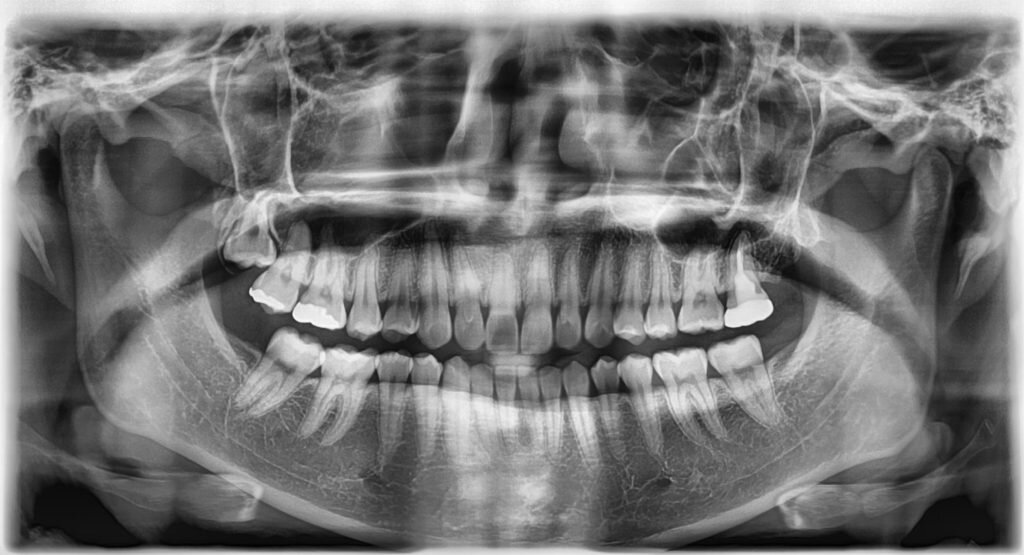

▫️ОПТГ (ортопантомограмма) - обзорный снимок обеих челюстей, показывающий общую картину состояния зубочелюстной системы. Врач может определить:

ОПТГ

- наличие кариозных полостей, в т.ч. скрытых

- патологию пародонта

- кистозные образования и скрытые воспалительные процессы

- качество пломбирования каналов и состоятельность пломб

- положение зубов относительно друг друга

- расположение непрорезавшихся зубов мудрости и их стадию прорезывания

- структуру тканей вокруг зуба